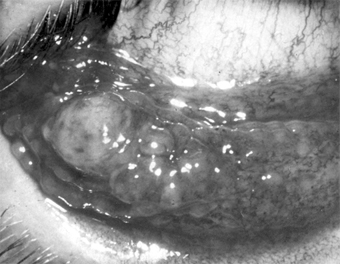

SUBCONJUNCTIVAL HEMORRHAGE

This common disorder may occur spontaneously, usually in only one eye, in any age group. Its sudden onset and bright red appearance usually alarm the patient. The hemorrhage is caused by rupture of a small conjunctival vessel, sometimes preceded by a bout of severe coughing or sneezing (Figure 5-24).

Figure 5-24

Figure 5-24: Subconjunctival hemorrhage.

The best treatment is reassurance. The hemorrhage usually absorbs in 2-3 weeks.